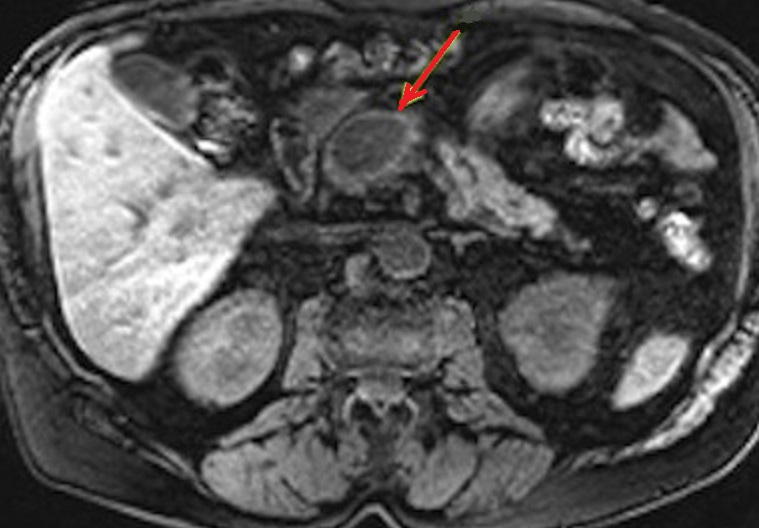

Image

radiologique IRM pondere sur T1 d'une pseudo kyste

du pancreas . Aspect radiologique est une kyste

ovalaire de hyposignale a bord epaisse ,

regulier lisse situe du corp du pancreas ( fleche

rouge ) . Image radiologique IRM ponderee T1 en

coupe axiale |